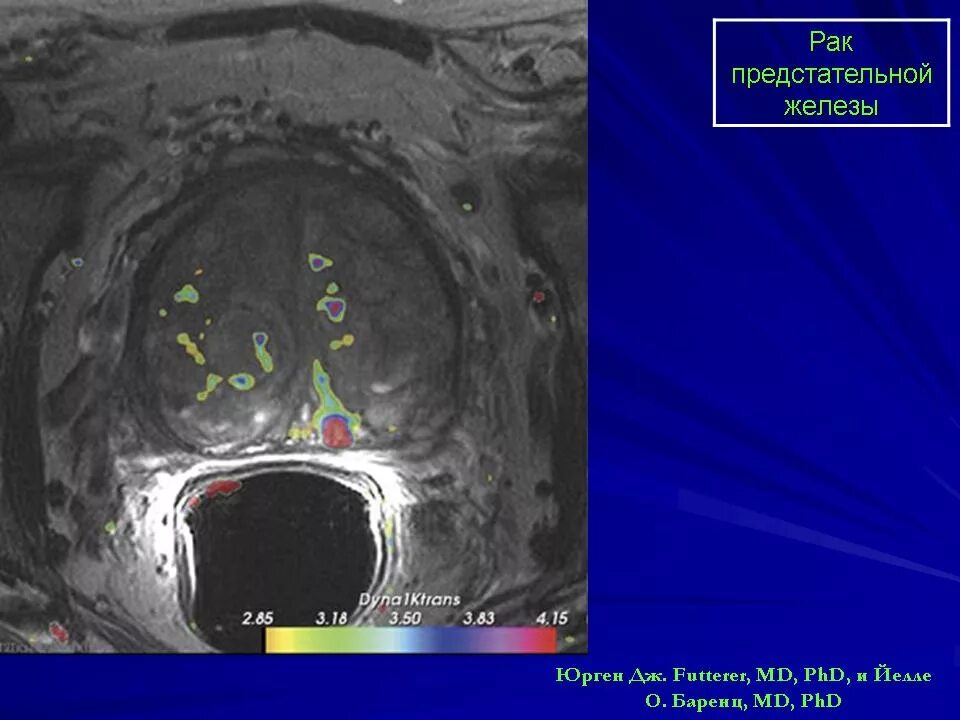

УВТ предстательной железы. Кальцинат предстательной железы. Cancer предстательной железы Предстательная железа MRT. Мультипараметрическое мрт предстательной железы. Предстательная железа кт норма. Аденома предстательной железы мрт

Предстательная железа MRT. Мультипараметрическое мрт предстательной железы. Предстательная железа кт норма. Аденома предстательной железы мрт Гистосканнинг предстательной железы. Трансректальная биопсия предстательной железы под контролем УЗИ. Ангиография предстательной железы. Лимфоузлы в предстательной железе